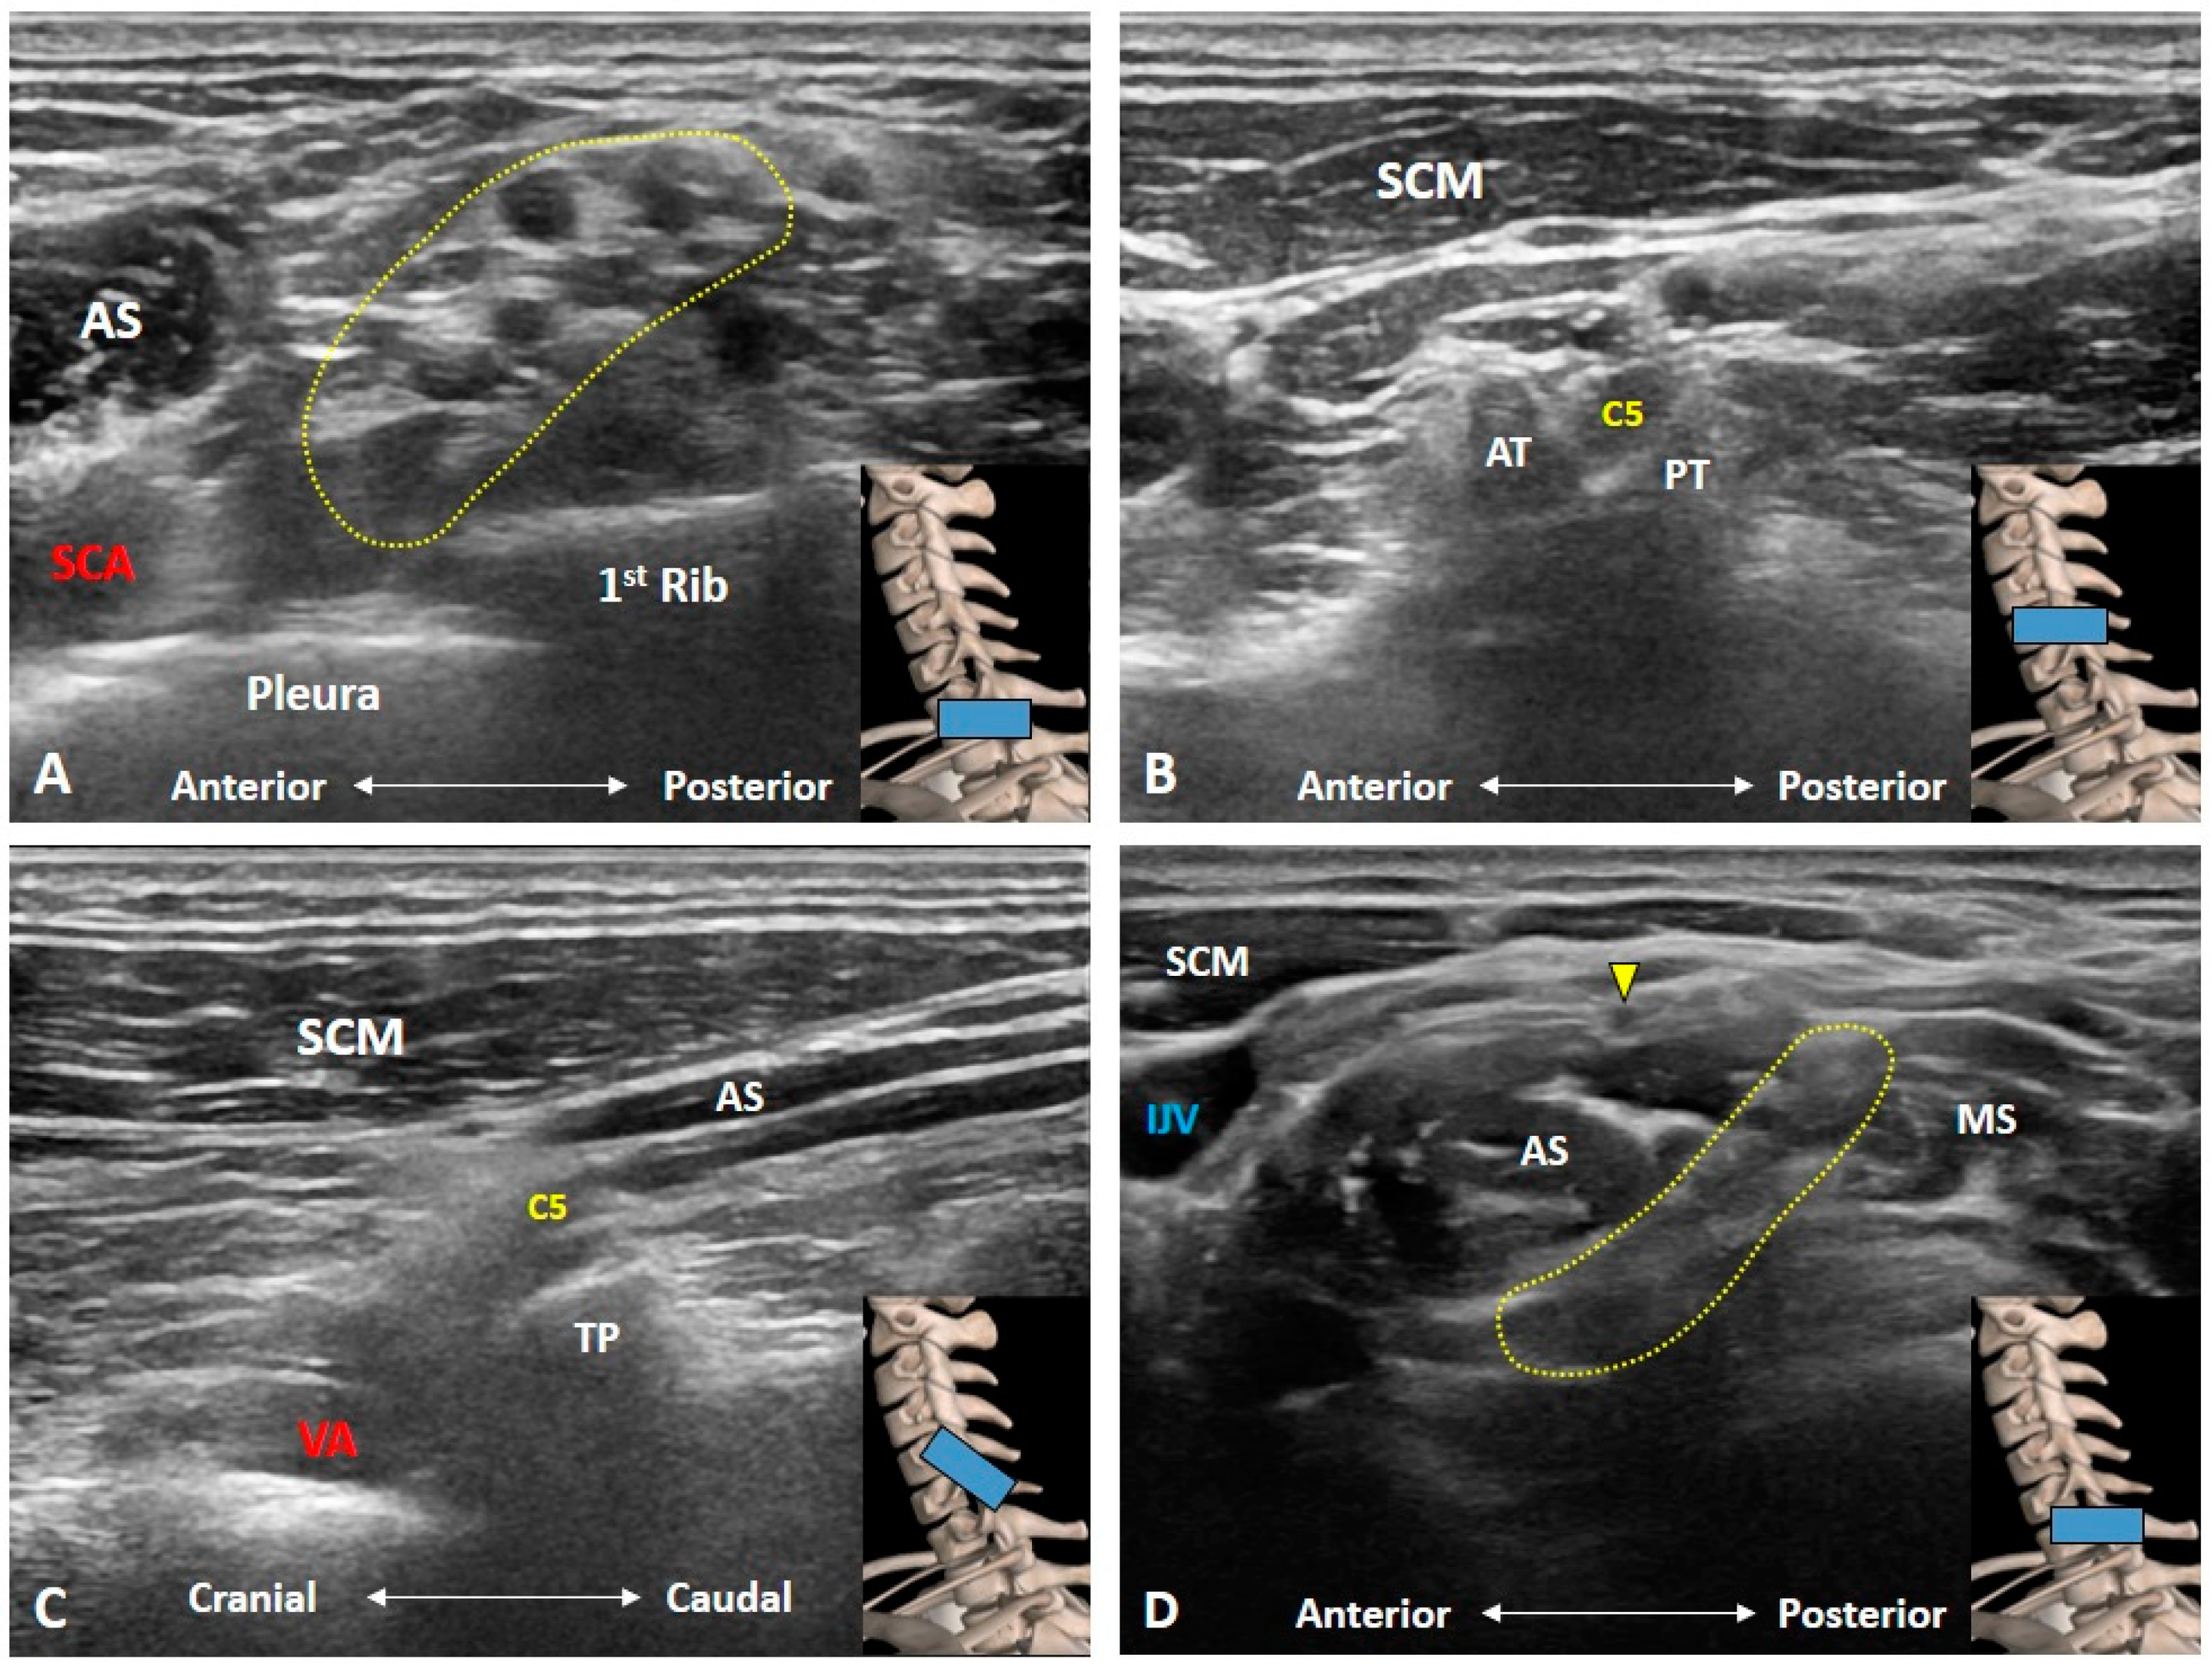

3. Imaging for Normal BP

3.1. Should We Start the Scanning Cranially?

3.2. Is the C7 Transverse Process Easily Recognized?

3.3. How Can We Locate the C8 and T1 Roots?

3.4. How Can We Better Visualize Cervical Anterior Rami during the Scanning Process?

3.5. Which Vascular Structure(s) Should We Be Aware Of?